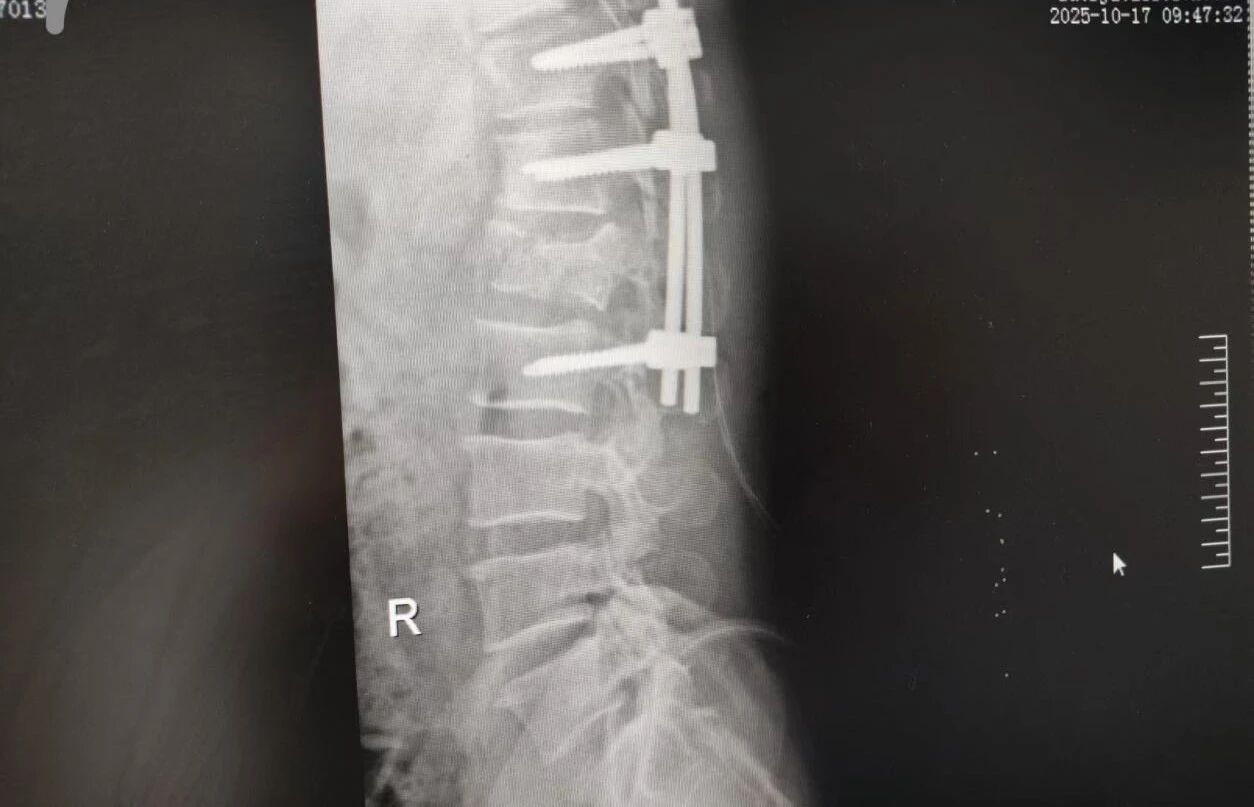

63 歲的王先生(化名)高空作業(yè)時(shí)不慎墜落,由漯河市中醫(yī)院急診科緊急接診。入院時(shí),他已生命垂危,初步檢查結(jié)果觸目驚心:腰 1 椎爆裂性骨折(脊柱嚴(yán)重?fù)p傷,隨時(shí)面臨永久性癱瘓風(fēng)險(xiǎn))、多發(fā)肋骨骨折伴血?dú)庑嘏c肺挫傷(胸腔 “堡壘” 重創(chuàng),呼吸功能幾近崩潰)。任一傷情皆足以致命,多重重創(chuàng)更讓其陷入生死絕境。

針對腰椎傷情,骨科竇志剛醫(yī)生團(tuán)隊(duì)緊急開展腰 1 椎體爆裂性骨折切開復(fù)位內(nèi)固定術(shù) + 椎板切除減壓術(shù)。手術(shù)室、麻醉科無縫銜接開通綠色通道,手術(shù)團(tuán)隊(duì)快速就位,術(shù)后患者下肢活動恢復(fù)自如。